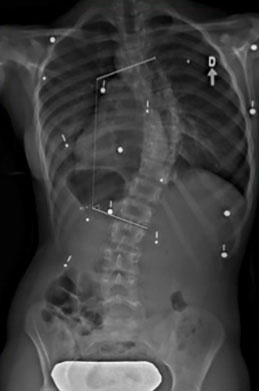

Étude de cas d’une autre adolescente avec une scoliose

Le cas d'une adolescente âgée de 12 ans et 9 mois (Risser 0) au début du traitement.

Cette jeune fille, dont la photographie montre une difformité importante du dos, souffre d’une scoliose déjà sévère dont la courbe atteint 42° (angle de Cobb) au début du traitement.

Dès l'installation du SpineCor®, on note une réduction de la courbure grâce à l'action dynamique des bandes élastiques malgré une scoliose très importante.

Après 30 mois de traitement, la scoliose est stabilisée à 33° et la croissance terminée. Il est normal avec une courbure d'amplitude aussi marquée de remarquer une légère perte de correction par rapport au premier jour du traitement, car la colonne vertébrale de la patiente a continué de grandir durant le traitement et la courbe d'évoluer. Quand on débute plus jeune le traitement sur des scolioses de moindre amplitude, il est souvent possible d'éviter ces phases d'aggravation.

Mais au final, la dernière photographie prise après le sevrage du traitement montre clairement que la posture de la jeune fille présente un aspect beaucoup plus normal et symétrique qu'au début. Grâce à SpineCor®, l'esthétique de son dos s'en trouve améliorée encore plus que la correction réelle de sa courbe, ce qui aura inévitablement un effet positif direct sur son image de soi.